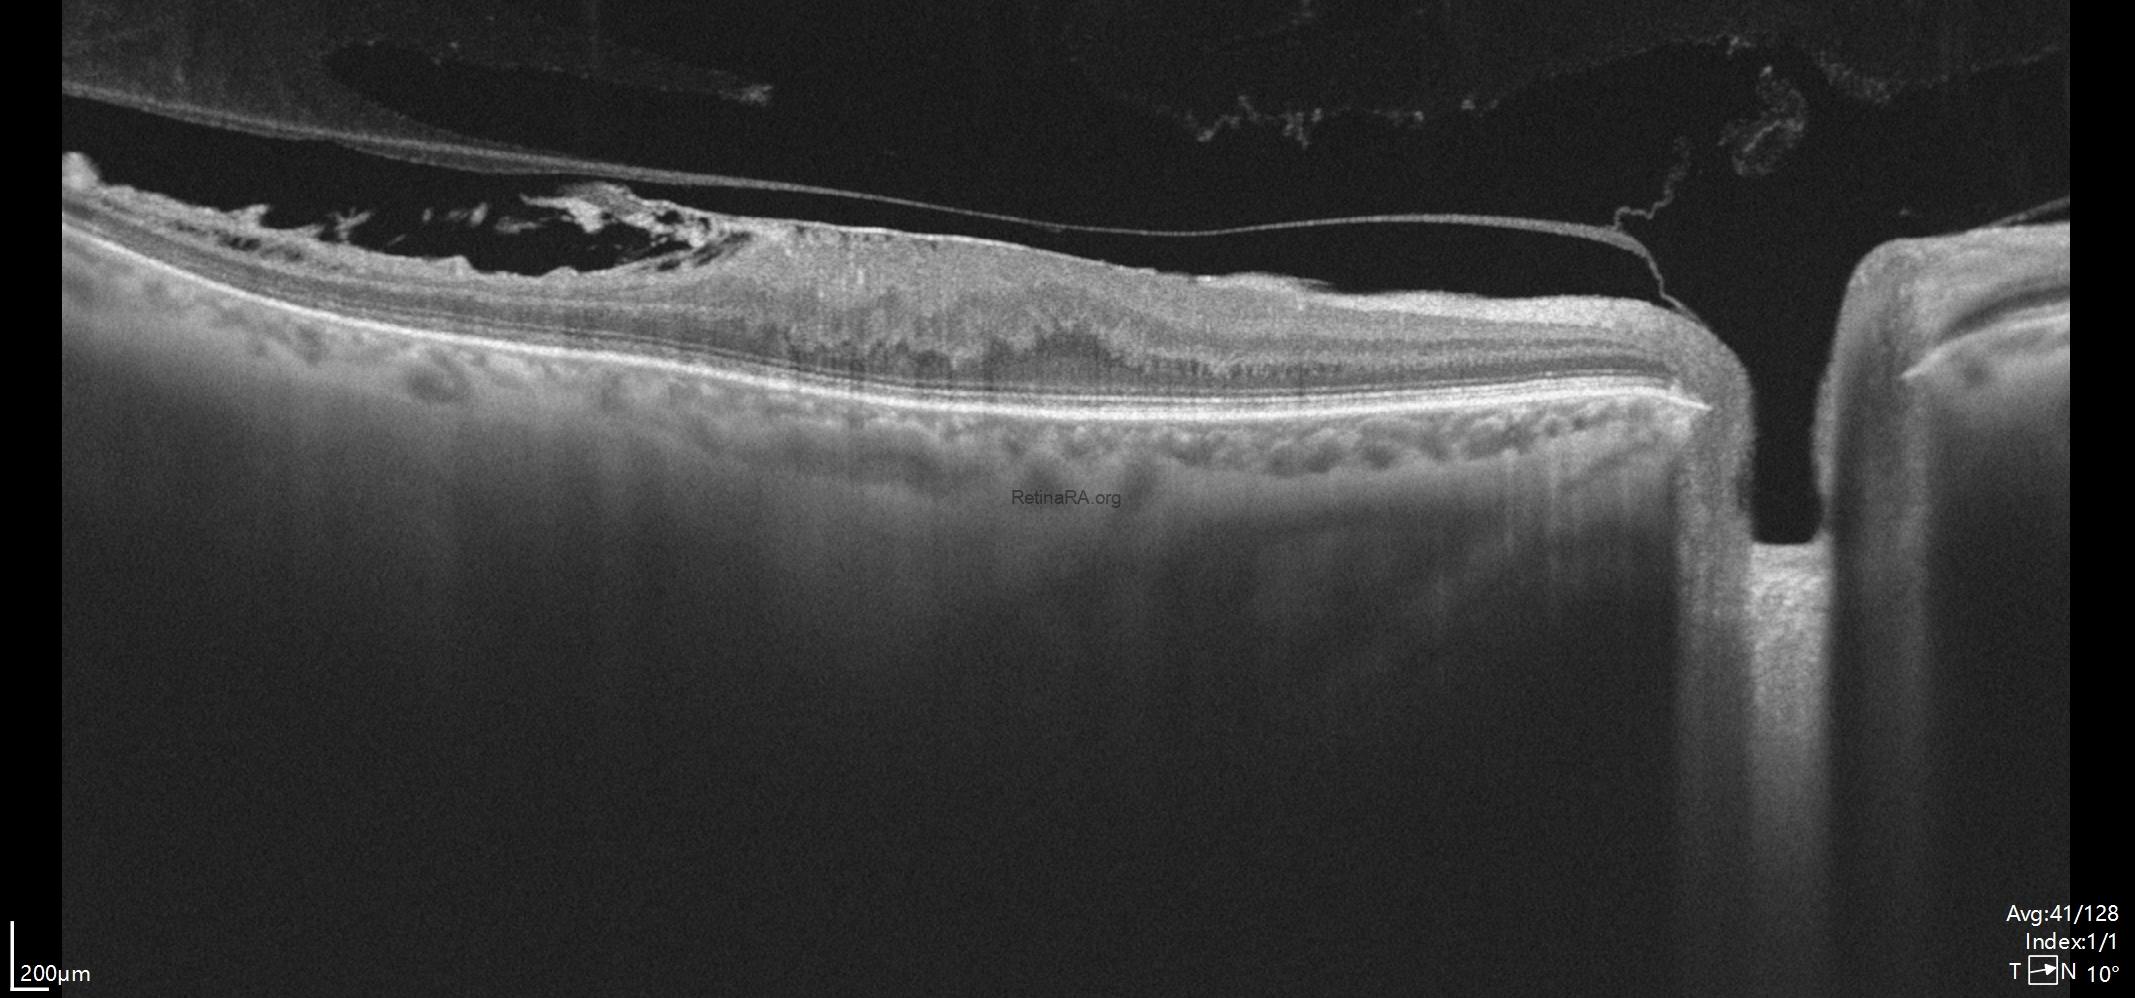

B-scan OCT shows us the loss of foveal depression due to ERM. In the upper scan, the posterior hyaloid appears attached to the optic disc. The lower OCT scan shows that, the posterior hyaloid remains attached to the retina in the temporal macular region where the retinoschisis appearance and damaged retina were present.

In the upper OCT, marked thinning of the temporal retina was visible. Disruptions were observed especially within the retinal nerve fiber layer and the ganglion cell layer.